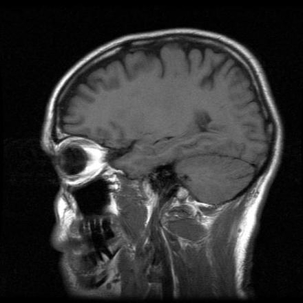

When a traumatic brain injury (TBI) is sustained, it can be difficult or impossible for the victim to fully recover. The function of the brain can be permanently affected and victims can be left cognitively impaired, suffering from memory loss or mood swings, and coping with a whole host of other serious health issues. Unfortunately, in the event that the brain injury victim is a child, the long-term effects could be even worse because the developing brain is hurt.

A child who sustains a traumatic brain injury needs extensive medical intervention. Unfortunately, a recent study showed that money affects the likelihood of a child getting appropriate care. Children are much less likely to receive the necessary rehabilitation if they come from poor families and/or if they come from families where English is not spoken as a first language.